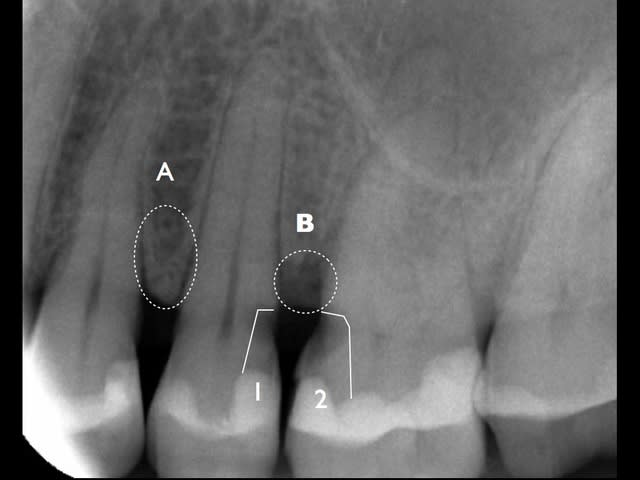

En A l'os est OK, l'espace biologique OK.

En B l'os est atteint et l'espace biologique perturbé.

Les lésions carieuses sont à distance de la pulpe, on n'a pas de perforation.

Objectif 1 rétablir un espace biologique inter-dentaire valide.

Objectif 2 préserver la pulpe vitale.